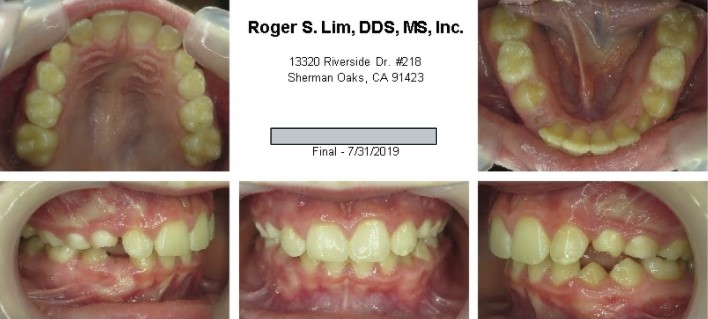

Before orthodontics

Before Maryland Bridges

During orthodontics

After Orthodontics & Bridges